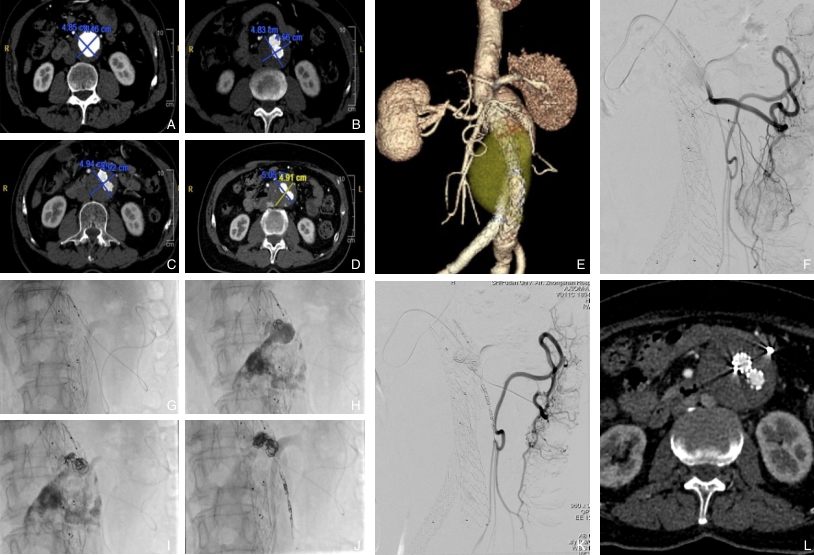

图3 未接受预防性IMA栓塞患者术后因IMA相关内漏瘤体持续增大接受再干预 A:干预术前;B-D:进行EVAR治疗后,AAA最大径在术后4个月及1、2年持续增长;E:术后3年CTA,可见IMA与瘤体沟通;F:DSA进一步明确IMA为Ⅱ型内漏来源;G-K:自肠系膜上动脉经分支选入IMA并进入瘤体,使用弹簧圈对瘤体及IMA进行栓塞,最终造影证实栓塞效果良好;L:干预后3个月随访,瘤体稳定Fig.3 Reintervention for persistent aneurysmal sac enlargement caused by IMA-related endoleak in a patient without prophylactic IMA embolization A: Preoperative imaging; B-D: Progressive aneurysmal sac enlargement at 4 months and 1 and 2 years after EVAR; E: CTA at 3 years showing communication between the IMA and aneurysmal sac; F: DSA confirming the IMA as the source of type Ⅱ endoleak; G-K: Coil embolization of the aneurysmal sac and IMA via the superior mesenteric artery; L: Follow-up imaging at 3 months after reintervention showing a stable aneurysmal sac